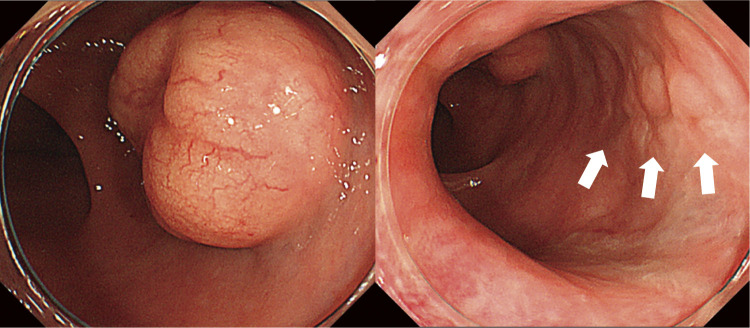

Case presentation: A 29-year-old woman experienced a severe perineal tear during the first vaginal delivery, which led to the incidental discovery of a 20-mm rectal NET. Four months after the perineal tear, the gynecology and digestive surgery teams ensured that the tear wound had completely healed and anal function was preserved. The patient underwent robot-assisted ultra-low anterior resection with lymph node dissection. The procedure was successfully completed, preserving anal function, and histopathology confirmed an NET (G2, pT2N2aM0, pStage IIIB). The patient recovered smoothly and was discharged on the seventh postoperative day.